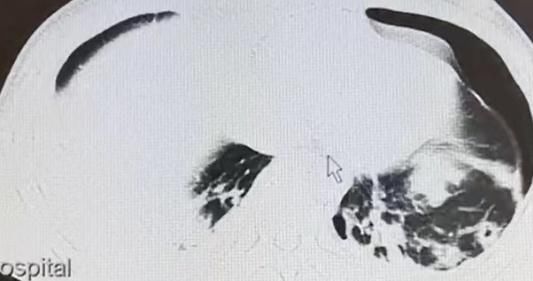

4月22日,因病情严重,罗某被送往遵义医科大学附属医院。医院急诊科刘同英医生说,罗某颅脑CT右侧颞顶叶脑出血、右侧颞顶叶脑水肿,左侧肺少量液气胸、右侧肺有少量胸腔积液。此外,他的肝右叶也受到了损伤。结合检查结果,医生讨论后认为,罗某生活在寄生虫感染区,有疫水接触及生吃螃蟹的情况,考虑其感染了寄生虫。